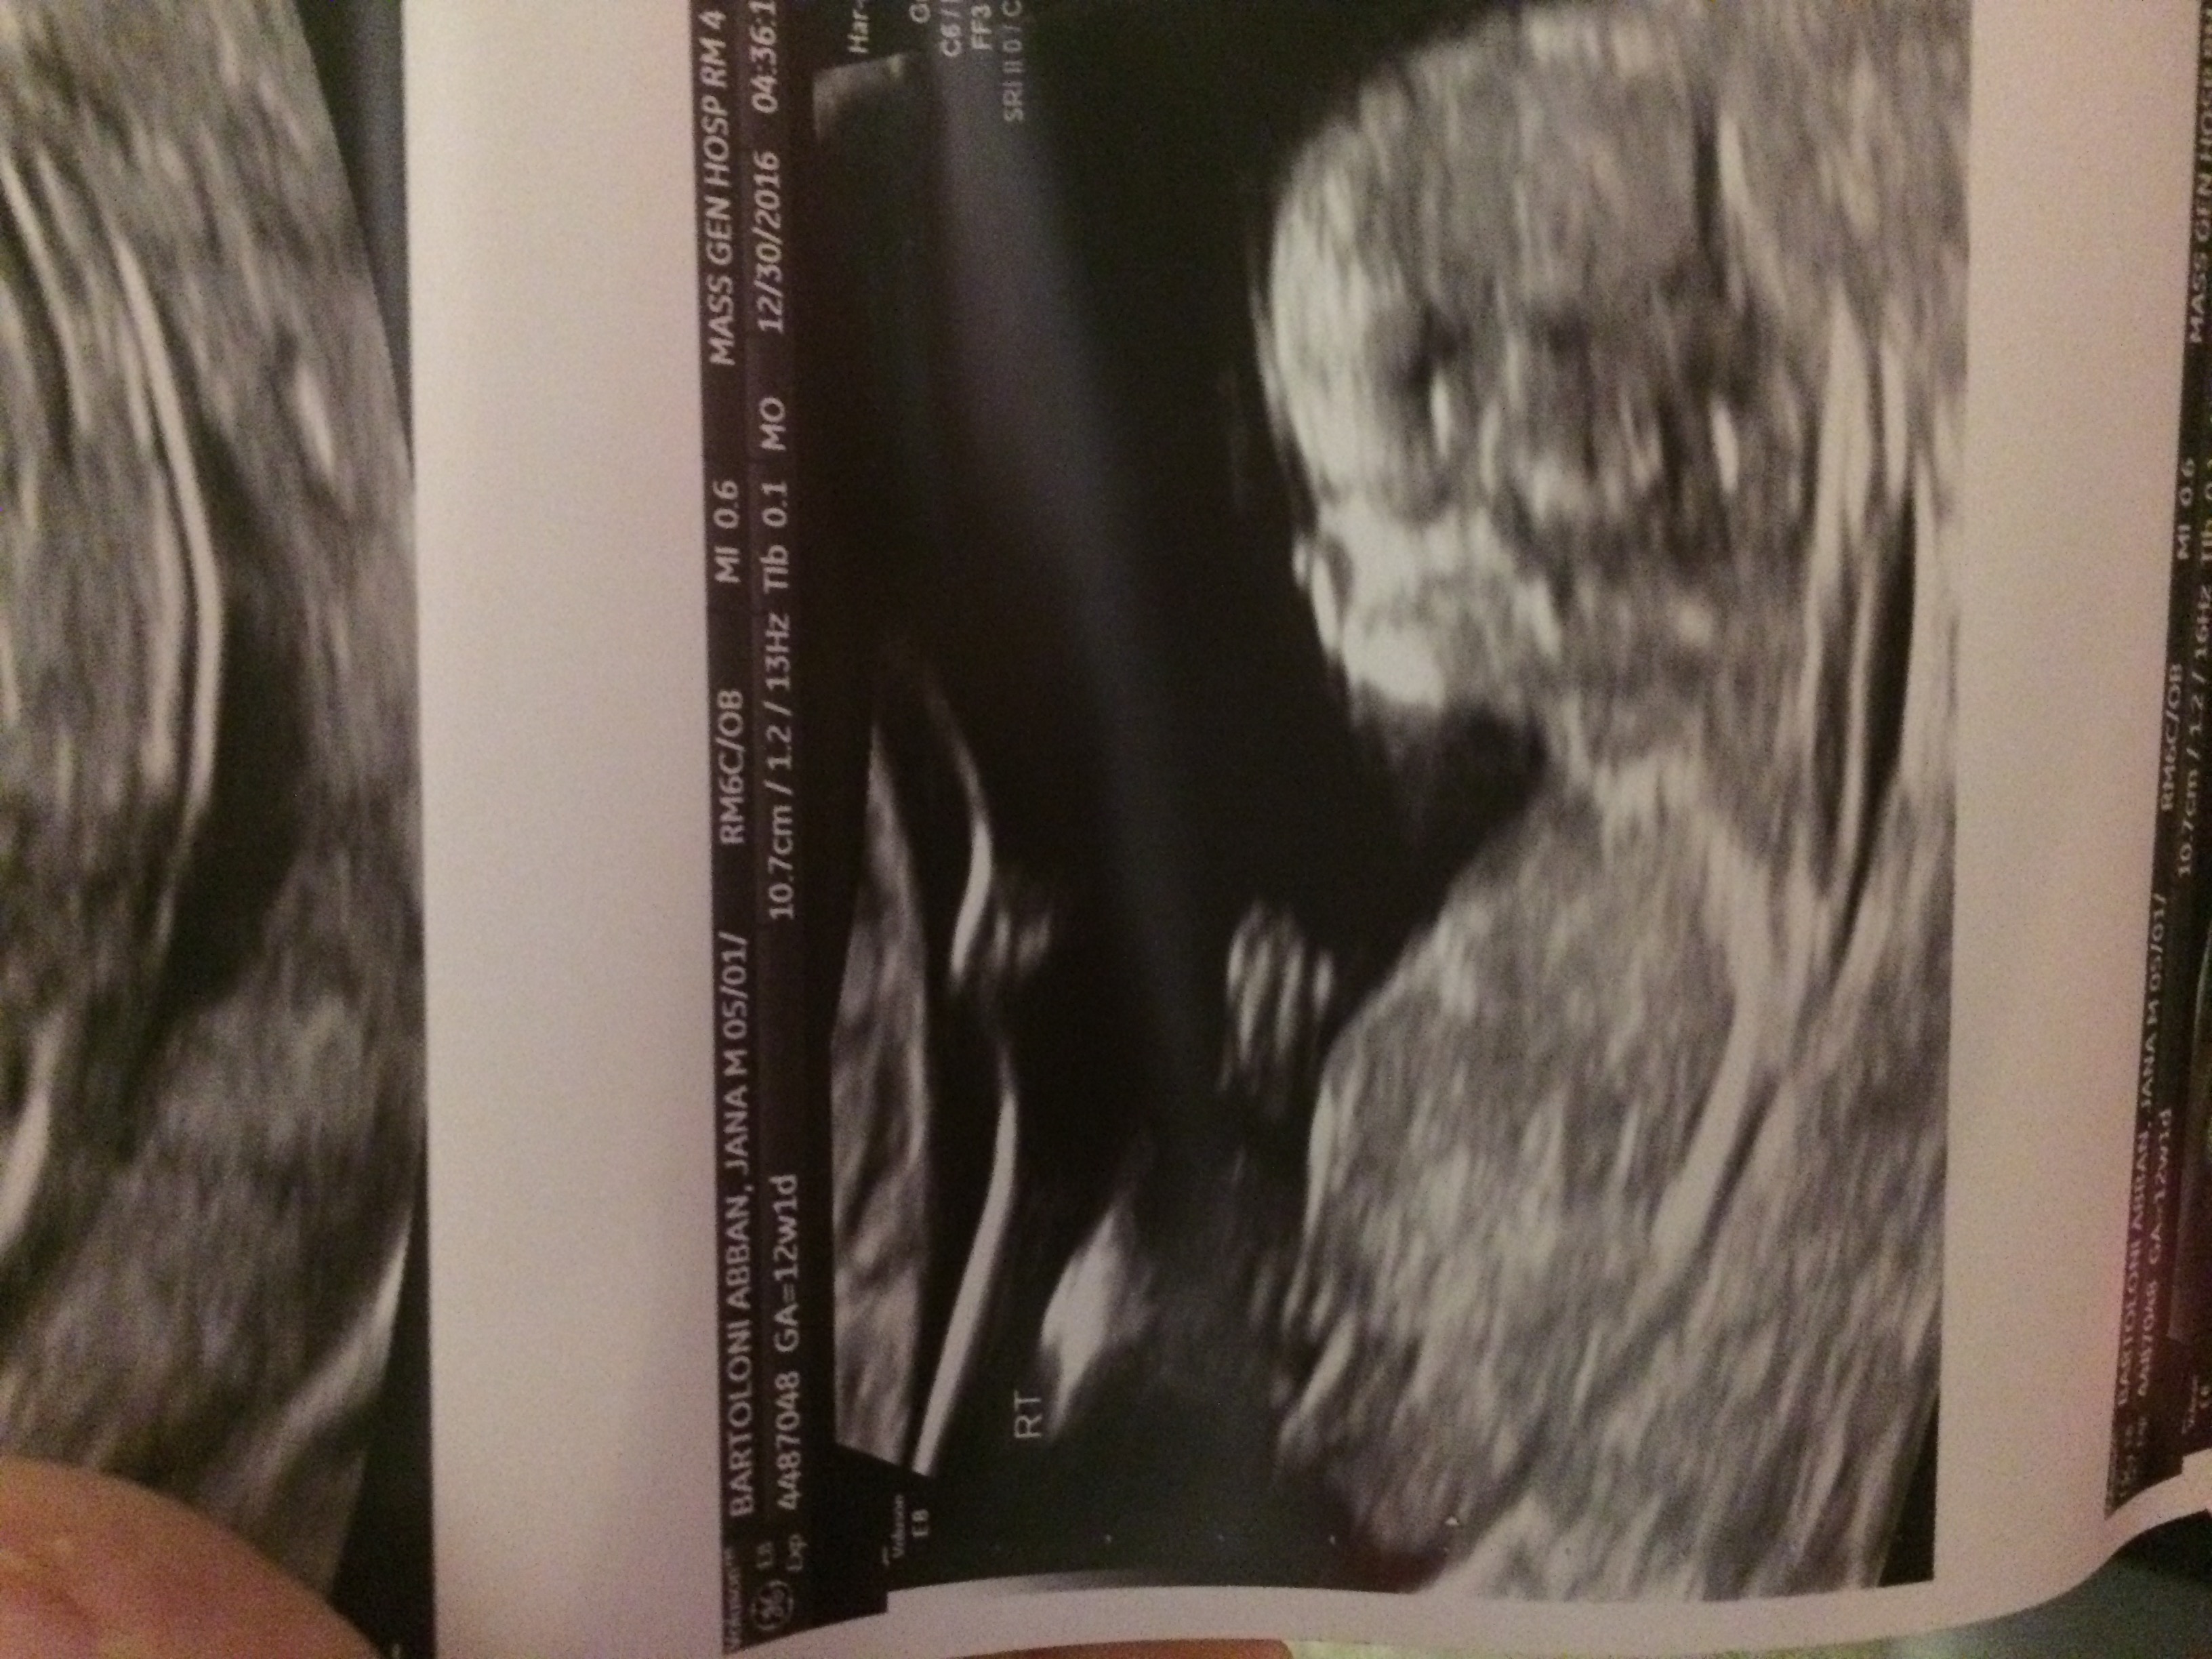

I just had my nt scan for twins and would love any guesses on gender. I only got a few pics and these were ones that had head to bum of both babies. Attachment 34245 Attachment 34246

It's very early as the nub could still rise, am only guessing. In both photos the nub, to my eye, is the long white line that is forked at the end. It appears to be parallel with the spine at this early gestation, it could rise and then that would indicate boy. What you hoping for? I hope some others offer a guess x

Top one is a girl. The bottom one I am leaning boy. But it is not clear. Congrats!

Top one girl, bottom one I'm not sure. Could be stacking there, but difficult to say, could also be girl.

So because the top one is straight and white that represents girl nub? And bottom could be boy because there are two lines at the end of the white line? Sorry I'm so new to this and appreciated all the guesses and explanations.

Earlier than I like to guess, but both babies look like girls to me.